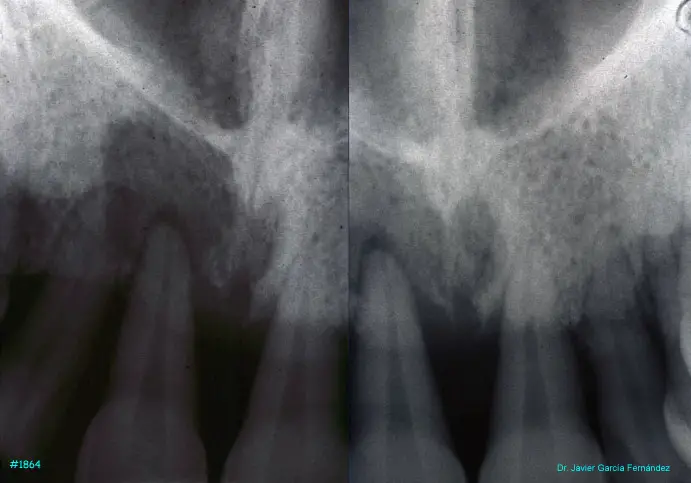

image 15